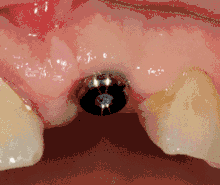

1. انعكاس الأنسجة الرخوة: يتم إجراء شق على قمة العظم، ويتم دفع حواف الأنسجة لامكانية إظهار العظم لوضع الغرسة. مع ذلك هناك تقنية بديلة، حيث تتم إزالة جزء صغير من الأنسجة (قطر الغرسة) لوضع الغرسة بدلاً من رفع حواف الأنسجة.

5. تكيف الأنسجة: يتم وضع وتكيف اللثة حول الغرسة بأكملها لتوفير شريط من الأنسجة السليمة حول الدعامة المربوطة بالغرسة. على النقيض من ذلك، يمكن "دفن" الغرسة، حيث يتم إغلاق الجزء العلوي من الغرسة بمسمار كغطاء ويتم إغلاق الأنسجة لتغطيتها بالكامل. في هذه الحالة، يلزم إجراء ثانٍ للكشف عن الغرسة في زيارة لاحقة للطبيب.